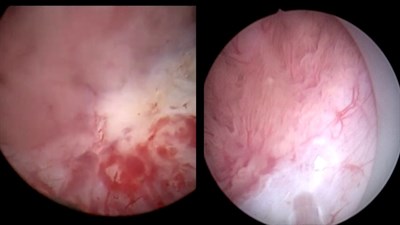

Лазерная тулиевая en-block резекция стенки мочевого пузыря с опухолью

Операцию проводит доктор медицинских наук, врач уролог онколог Николай Иванович Сорокин.